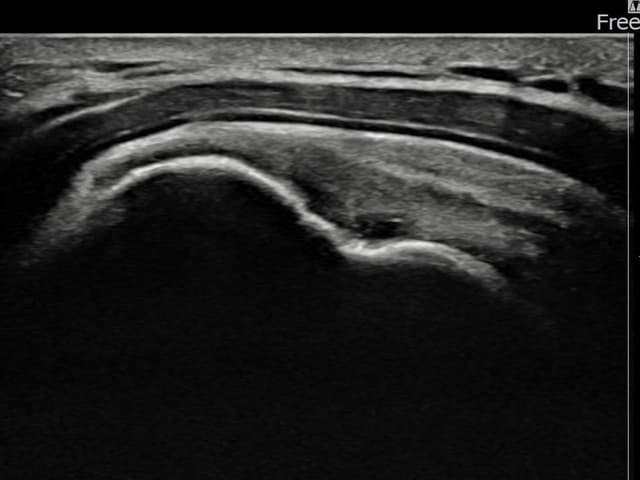

[経過期間: 23.07.31~23.09.27]

[縫縮術] 超音波検査にて左 棘上筋腱 부착부 광범위 部分断裂(13mm × 5mm (腱厚の約65%欠損))を確認。縫縮術施行後、腱の連続性が回復し、日常生活に復帰されました。